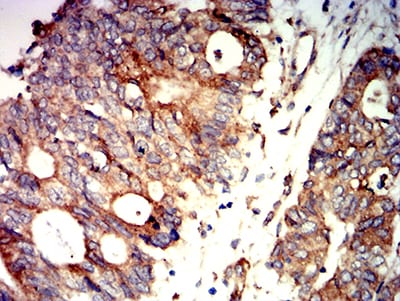

![PRKAB2 Mouse mAb[64124]](https://img1.dxycdn.com/p/s14/2025/0922/773/0080669378327699691.jpg)

Immunohistochemical analysis of paraffin-embedded human cervical cancer tissues using PRKAB2 mouse mAb with DAB staining.